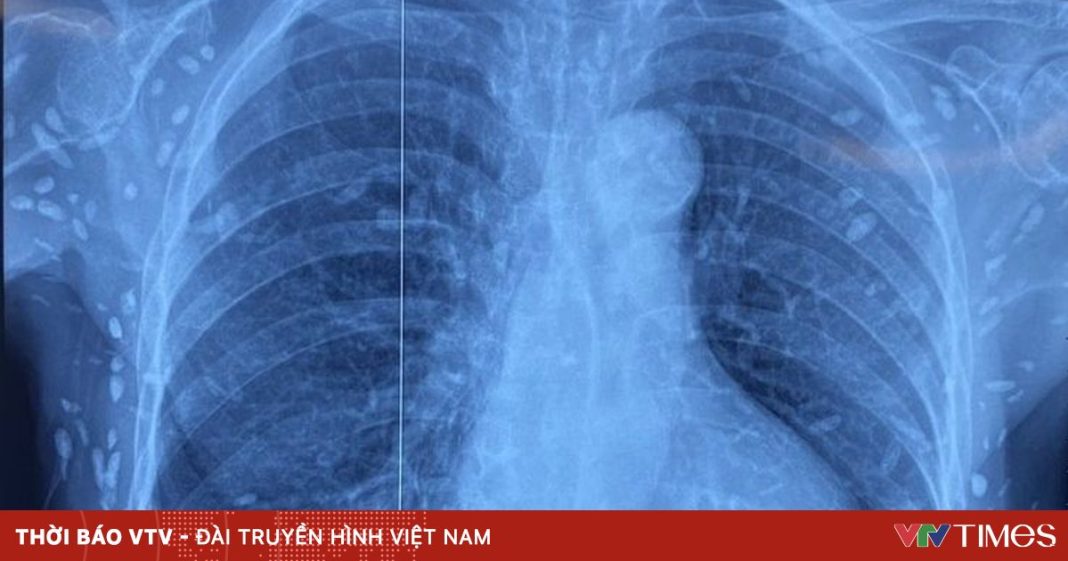

Người bệnh được chuyển đến Viện Lâm sàng các bệnh Truyền nhiễm trong tình trạng rối loạn ý thức, đe dọa suy hô hấp. Kết quả chụp cắt lớp vi tính sọ não và X-quang ngực – bụng cho thấy rất nhiều nốt cản quang nằm rải rác trong nhu mô não và dưới da vùng ngực, bụng, tay. Một số u cục có thể sờ thấy bằng tay.

Theo bác sĩ điều trị, mặc dù xét nghiệm kháng thể IgM âm tính, hình ảnh tổn thương đặc trưng gợi ý người bệnh từng bị nhiễm ấu trùng sán dây lợn (Taenia solium), các nang sán đã vôi hóa và tồn tại lâu dài trong mô. Bệnh nhân được điều trị theo phác đồ, đáp ứng tốt và được cho ra viện tiếp tục theo dõi.